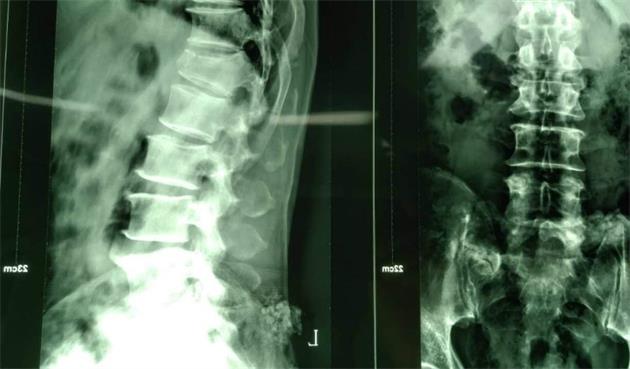

該系統(tǒng)是針對(duì)胸腰椎后路微創(chuàng)手術(shù)設(shè)計(jì)的經(jīng)皮內(nèi)固定系統(tǒng),采用“自通道”設(shè)計(jì),置釘時(shí)無(wú)需釘尾延長(zhǎng)裝置,簡(jiǎn)化了微創(chuàng)手術(shù)經(jīng)皮固定的操作步驟,顯著地縮短了手術(shù)時(shí)間。同時(shí),超長(zhǎng)的釘尾設(shè)計(jì),超重患者不再是顧慮,適用范圍更廣!